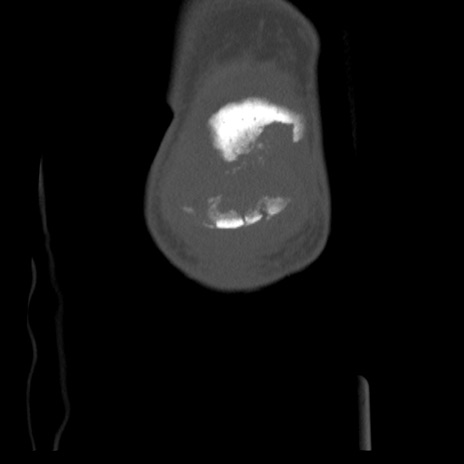

右膝関節CT

横断像